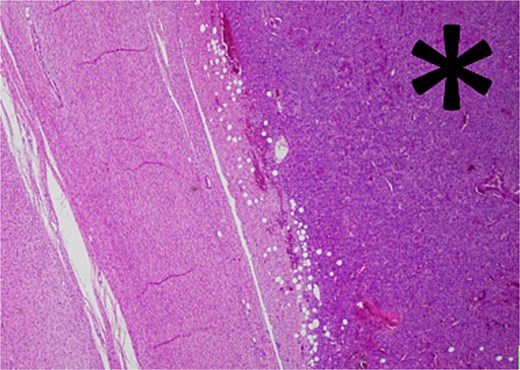

Histology revealed a multilobulated spindle cell lesion, with low- and high-grade areas, with an abrupt transition between these areas. There was an adjacent focus of adipose tissue with rare cytologic atypia suggestive of possible WDL, which indicated that the tumor mass may represent DDL. However, there was a single focus of lipoblasts identified, bringing up the differential of pleomorphic liposarcoma. Therefore, in situ hybridisation was performed and showed MDM2 amplification, which confirmed the diagnosis of DDL, with likely homologous lipoblastic morphology. The tumour was excised with clear margins (Figs 3–8).

Low-grade component with abrupt transition to high-grade component (asterisk).